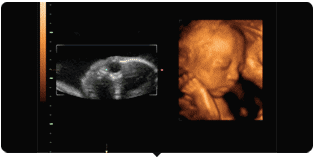

玛丽—— GE-S6四维彩超

许昌玛丽妇科医院拥有目前许昌的四维彩超监测仪——GE-S6四维彩超,它是利用出色的人体工程学设计,不存在辐射,对宝宝来说是的安全。与其它超声诊断过程相比,它可以实时的观察人体内部器官的动态运动,可以检测和发现各种异常。在目前超声领域,GE-S6四维彩超的畸形筛查、成像效果遥遥于其他设备。(建议阅读:胎儿写真,“四维彩超”检查火爆)

【四维图像】

麻麻,我在挠耳朵~